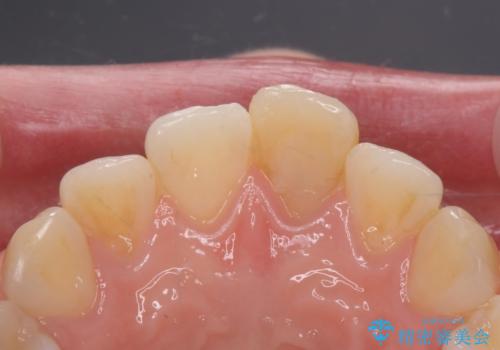

前歯の変色とガタつき ジルコニアクラウンでの修復

- 前歯の変色とガタつきが気になるとのことで来院された患者様です。

根管治療からやり直しを行った後、ジルコニアクラウンで修復することで、ガタつきと変色の両方を改善していきます。

ガタつきと変色の両方を改善することができ、大変喜んでいただけました。

少しのガタつきであれば、矯正治療を行わなくても改善できる場合があります。